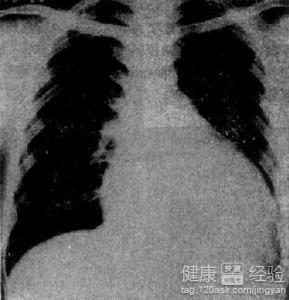

擴張性心肌病是一種人體的心肌疾病,此病主要表現在我們人體的左心室或者右心室擴大,有的也是兩側都擴發,並且還會有功能減退的現象,此病若是病情加重,很容易會使患者出現死亡。此外像服用了抗癌的藥物,或者精神受到刺激都可能會引起這個病。這個病比較常見的症狀有像呼吸困難,心律不齊等等,那麼在我們平常的生活中擴張性心肌病應該注意什麼呢?今天我就跟大家分享一下。